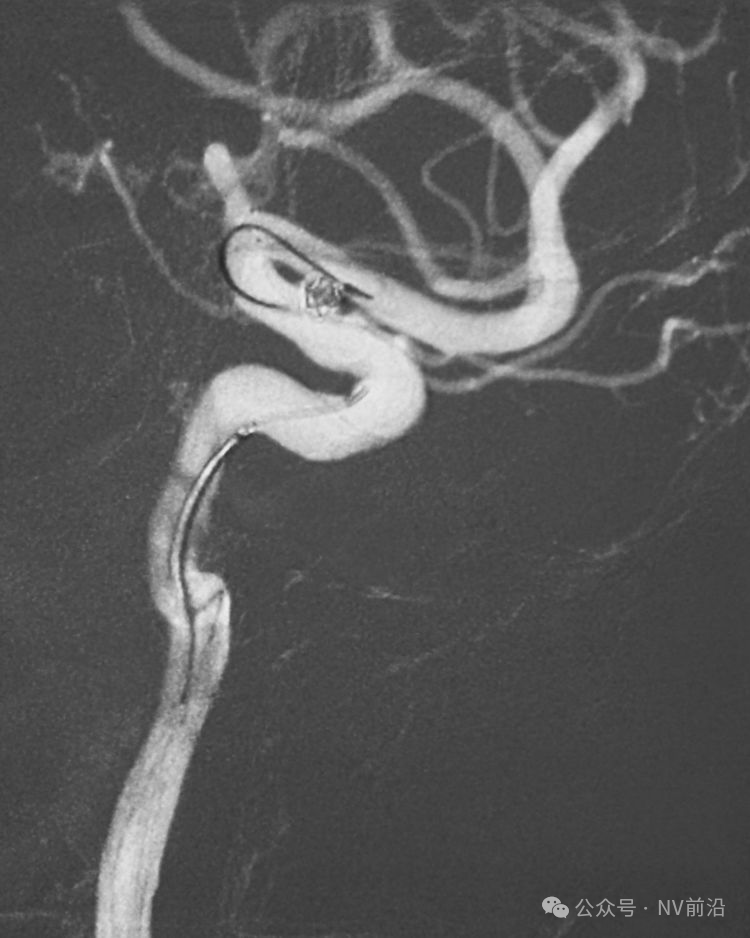

病例一,左侧微小眼动脉瘤,未破裂。

测量:瘤体2.09×2.34 mm,颈宽2.66 mm。

工作位造影

Traxcess 14微导丝可以进入瘤腔,但头端塑成S形的Echelon 10微导管无法跟入。

将微导管在虹吸弯处成襻,越过瘤颈,管头折返钩入瘤腔,即所谓回马枪技术。